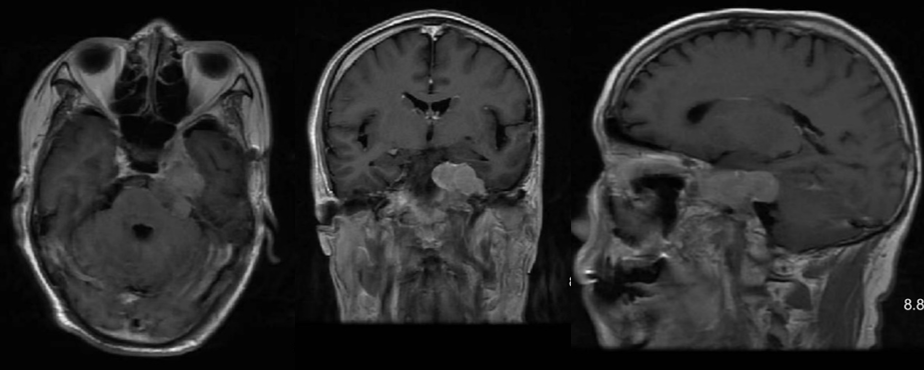

2024年7月复查头颅MRI提示硬膜下血肿已吸收,左侧海绵窦肿瘤快速增大(图4)。

遂收治入院计划手术治疗。由于肿瘤生长迅速,且伽马刀效果不佳,患者术前左眼视力已明显下降仅光感且有暴露性角膜炎,手术以尽可能全切肿瘤及基底、降低术后复发几率为首要目的,由于肿瘤包饶颈内动脉,术中需特别注意避免颈内动脉损伤。经医疗组、科室讨论,决定复合手术下经Kawase入路切除。

术后复查头颅CT未见出血、脑水肿,头颅MRI提示肿瘤全切(图6)。患者术后恢复良好,神志清,四肢肌力5级,左眼睑下垂,左面部麻木。